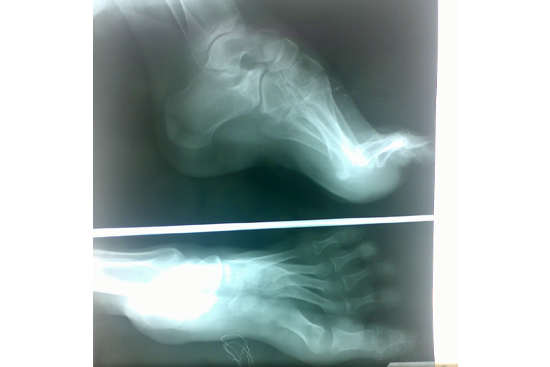

TEV

Aarti

Gulam Rasul